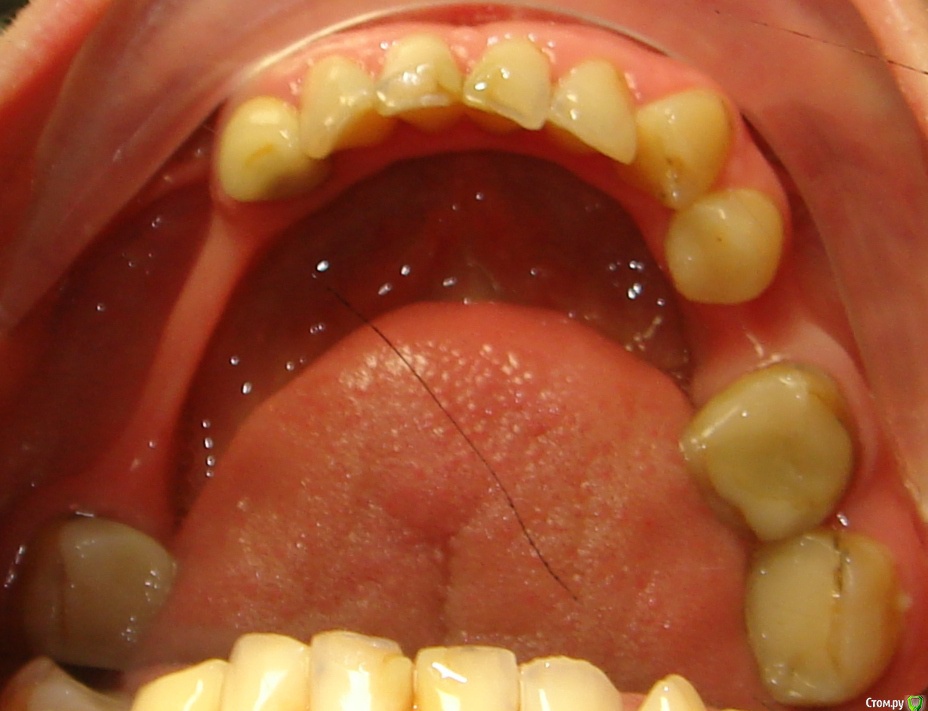

Здравствуйте, Коллеги! Хочу спросить совета по такому случаю. Пациентка 33 года. В детстве удалили 12 зуб, пространство закрыли на съемном аппарате. В подростковом возрасте удалили все остальные отсутствующие зубы. Сейчас носит бюгель. Вопрос такой: заниматься ли мне, как ортодонту формированием полноценного межчелюстного соотношения, или просто решить локальные проблемы и отдать на функциональную реабилитацию ортопеду? И если все-таки заниматься мне, то как??? Лечение такого третьего класса - элементарно для многопетлевой при наличии адекватной опоры, но вот такая адентия заставляет меня сомневаться. Заранее спасибо за ответы!